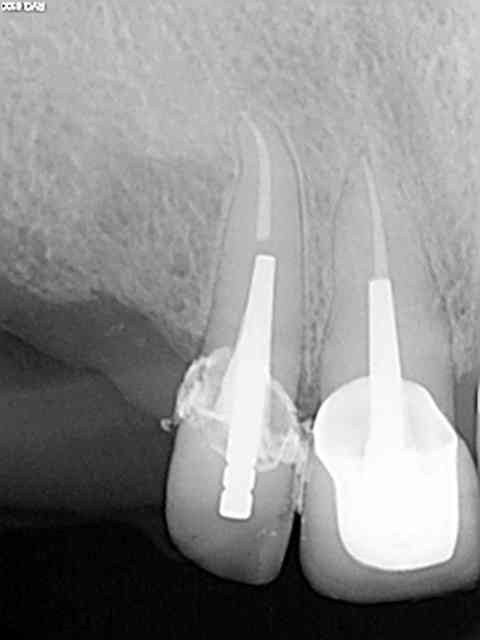

Exemple sur cette 12 tout à l'heure, 1h 30 de rdv terminé en 1h et encore j'ai un peu "tâtonné" pour trouver la pulpe. Toujours pas de cathétérisme manuel of course sinon j'y serais encore.)))))

R1 opftbj - Eugenol

R2 e2ugld - Eugenol

R5 pe3mvv - Eugenol

R3 vqepcx - Eugenol

R6 llenvb - Eugenol

R7 zpryie - Eugenol

R4 wce84r - Eugenol